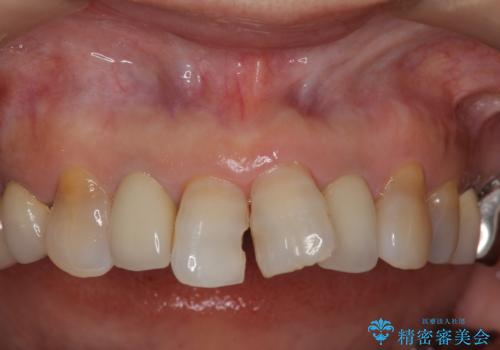

50代女性 前歯のつめものがとれた これを機に前歯をきれいにしたい

- 前歯の詰め物が頻繁に外れるとのことで来院。

これを機にセラミックでかぶせて、前歯の歯並びも良くしたいとのことでした。

両側の前歯もやり替えをすることで、前歯の前突感も無くしています。